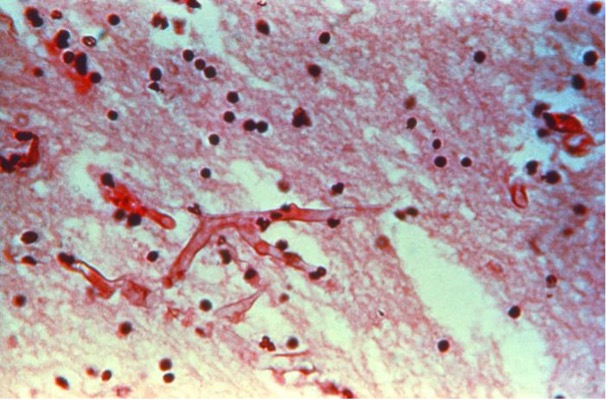

Daarnaast kunnen schimmelstructuren worden aangetoond met behulp van histopathologische kleuringen22,69. BAL en weefsels verkregen met biopsie zijn hiervoor de meest geschikte materialen. De standaard H&E (hematoxyline en eosine) kleuring wordt gebruikt om te bepalen of er sprake is van ontsteking, maar is niet specifiek voor schimmels. Desondanks kunnen hyfen en schimmels met deze kleuring wel worden opgemerkt. Bij vermoedens van een schimmelinfectie kan het nuttig zijn om aanvullend een PAS (Periodic Acid-Schiff) en een Grocott’s (Grocott-Gomori’s methenamine silver) kleuring uit te voeren. Hiermee worden schimmeldraden specifiek aangekleurd, waardoor deze beter zichtbaar zijn en gebruikt kunnen worden om schimmeldraden in weefsel te detecteren.

Een nadeel van microscopie is de beperkte gevoeligheid22,69. Met behulp van microscopie kunnen schimmeldraden worden aangetoond, maar betrouwbare identificatie van de schimmel is niet mogelijk. Als er gesegmenteerde schimmeldraden worden gezien met dichotome vertakkingen zou dit bij een Aspergillus infectie kunnen passen. Echter ook veel andere schimmels kunnen dezelfde kenmerken hebben. Bij infecties door Mucorales worden juist geen of weinig segmenten gezien in de schimmeldraden, zijn de draden erg wisselend van diameter en vertakken de schimmeldraden recht (op 90 graden) af.

Deze microscopiefoto van een met hematoxyline-eosine (H&E) gekleurd menselijk longweefselmonster, geoogst van een patiënt met pulmonale aspergillose, toont de histopathologische veranderingen door de aanwezigheid van Aspergillus sp. schimmelorganismen. Let op de vertakkende hyfen tussen het longweefsel.

Bron: CDC/ Armed Forces Institute of Pathology (AFIP); Dr. Hardin:

https://phil.cdc.gov/Details.aspx?pid=15630